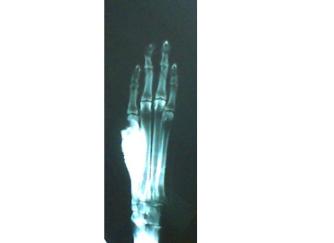

fungal

infection!